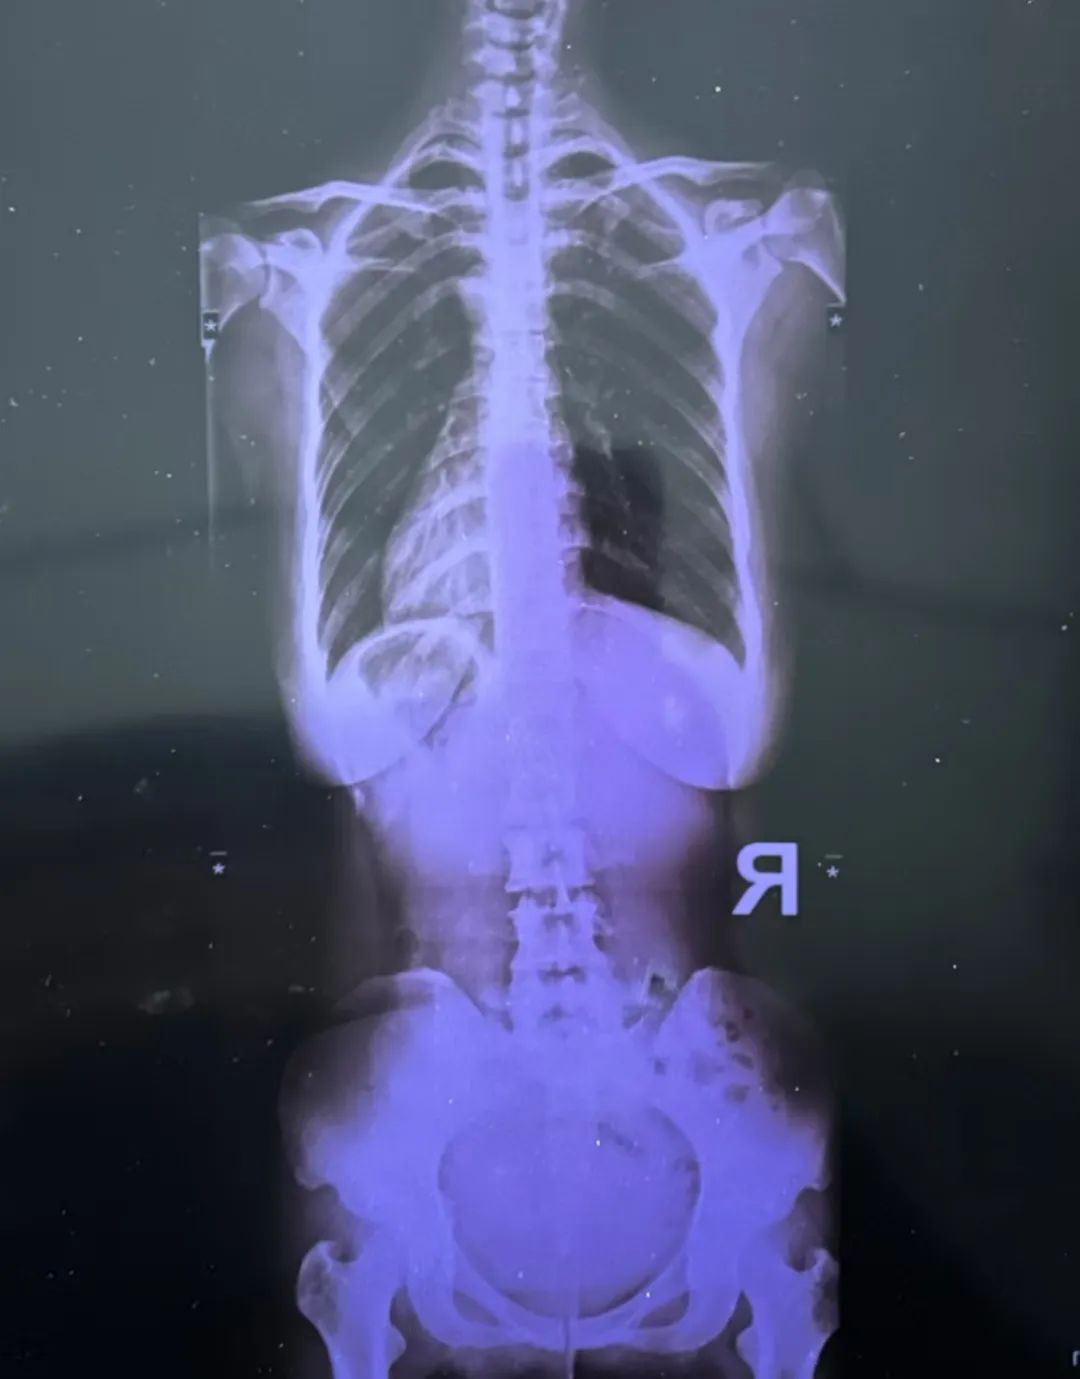

最近又疼起來嚴(yán)重影響正常生活,她前往醫(yī)院就診,結(jié)果查出了脊柱側(cè)彎11°,骨盆旋移,骶髂關(guān)節(jié)半脫位,由于這些導(dǎo)致頸肩,后背,腰部肌群代償出現(xiàn)問題,從而出現(xiàn)腰痛,后背痛,肩膀痛!

蘇鴻凱醫(yī)生根據(jù)王女士的具體情況,為王女士制定針對性治療方案,在治療中采用正骨手法復(fù)位,在配合結(jié)構(gòu)針法治療,來調(diào)節(jié)肌肉功能使恢復(fù)平衡。